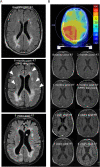

Results: MS neither predisposes nor protects from the development of gliomas. Patients with glioblastoma WHO grade 4 without isocitratdehydrogenase (IDH) mutations have a longstanding history of MS, whereas patients diagnosed with IDH-mutant astrocytoma WHO grade 2 receive multiple sclerosis diagnosis mostly at the same time or later. Concurrent MS is associated with a lesser extent of tumor resection and a worse prognosis in IDH-mutant glioma patients (PFS 32 vs. 64 months, p = 0.0206). When assessing tumor-intrinsic differences no distinct subgroup-defining methylation pattern is identified in gliomas of MS patients compared to other glioma samples. However, differential methylation of immune-related genetic loci including human leukocyte antigen locus on 6p21 and interleukin locus on 5q31 is found in MS patients vs. matched non-MS patients. In line, inflammatory disease activity increases in 42% of multiple sclerosis patients after brain tumor radiotherapy suggesting a susceptibility of multiple sclerosis brain tissue to pro-inflammatory stimuli such as ionizing radiation.

Conclusions: Concurrent low-grade gliomas should be considered in multiple sclerosis patients with slowly progressive, expansive T2/FLAIR lesions. Our findings of typically reduced extent of resection in MS patients and increased MS activity after radiation may inform future treatment decisions.